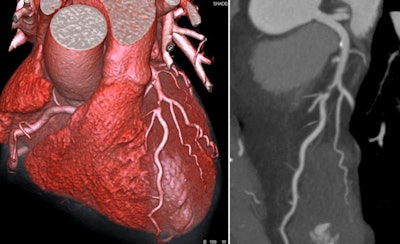

Achenbach is chairman of cardiology and a professor of medicine at the University of Erlangen, Germany, and he became ESC president in September 2020. He won the 2017 Minnie award for Most Influential Radiology Researcher. His research interests focus on cardiovascular imaging, mainly CT, for the early detection and characterization of coronary atherosclerosis, and for the support of coronary and cardiovascular interventional procedures.

A: As before, we are working on the relationship between cardiac imaging and cardiac intervention. This is what excites me most at this point in time.

Imaging is superbly important to permit and to move ahead all the new structural heart interventions.